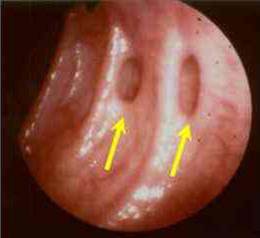

Colonoscopia: As setas indicam as áreas dos Divertículos.